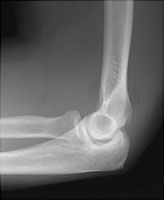

Radial head fractures are common and result from a fall on an outstretched hand. These fractures can be subtle and indirect signs are used to infer their presence. A visible posterior fat pat is the most sensitive indicator of an occult fracture. The "sail sign" or displaced anterior fat pad is also used to diagnose occult radial head fractures, but is less sensitive than displacement of the posterior fat pad.

- Click on the image for a larger versionALateral radiograph of the elbow. There is displacement of both the anterior and posterior fat pads.